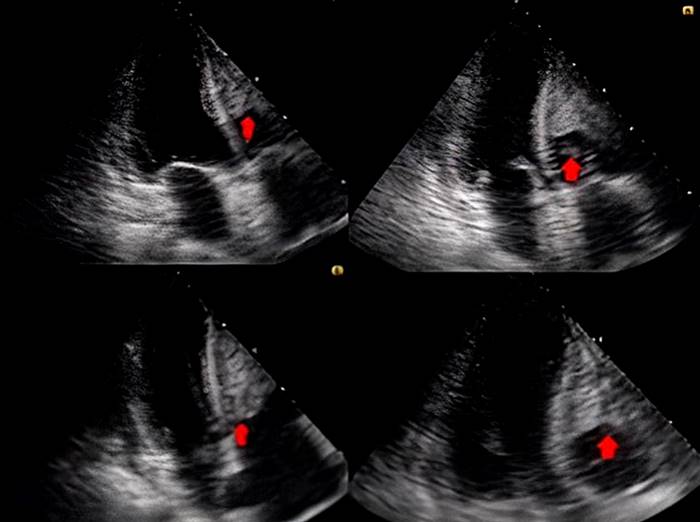

A chest CT confirmed the consolidation process and pericardial effusion (thickness: 7 mm). The transthoracic echocardiogram revealed a dilated right ventricle and two thrombi of equal echogenicity, one occupying most of the free wall and the other rounded, oscillating and protruding through the tricuspid valve (Figure 2), so anticoagulation with low molecular weight heparin (LMWH: 1 mg/kg/day) and diuretics was started.